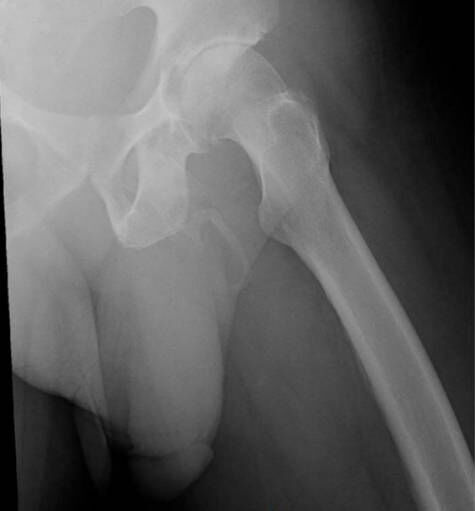

来自于《泌尿学病理报告杂志》的这份报告介绍,这名男子在人行道上摔到了臀部,就诊过程中他除了反应膝盖疼痛外,还说阴茎也很疼。医生为他做了骨盆X光检查,发现了一个奇特的事情:他的阴茎发生骨化,也就是长出了骨头。报告作者称,“阴茎骨化”情况目前非常罕见。

当钙盐在体内软组织积聚时,就会发生骨化,导致身体中有结缔组织的区域形成骨骼。这种疾病虽然罕见,但与一种名为佩罗尼氏病的疾病有关,也叫阴茎硬结症。这种疾病可发生在阴茎疤痕组织部位,导致阴茎弯曲,可能导致阴茎疼痛。